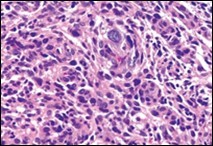

Ultrastructural evaluation is devoid of pertinent cellular features. However, modified endothelial cells, smooth muscle cells, striated muscle cells, histiocyte- like cells, fibroblast- like cells and miniature, interdigitating cellular processes conjoined by desmosome- like junctions are discerned5, 6. Figure 1, Figure 2, Figure 3, Figure 4, Figure 5, Figure 6, Figure 7, Figure 8.

Figure 2.Angiomatoid fibrous histiocytoma delineating sheets of spindle-shaped cells with bland nuclei and moderate cytoplasm disseminated in a vascularized stroma and a cuff of lymphoid cells 9.